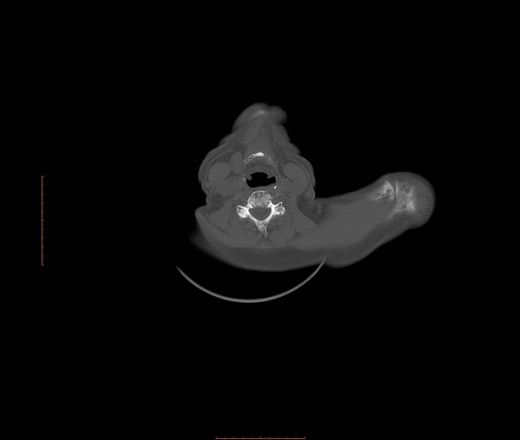

Пациент 1946 г.р., состоит на Д учете в онкодиспансере по поводу с-ч кожи (базалиома), прошел курс лучевой терапии, в 2009г на Ргенографии выявили образование 7 ребра, направили на Кт, на КТ (2009г) был выставлен д-з ГКО, пункционная биопсия не произведена. А сейчас вот такая картина, с множественными литическими очагами в костях грудного склета + образование 7 ребра, с отрицательной динамикой.

повторно взяли пациента, сняли кости таза, такая же картина- множественные очаги литической деструкции. Заключение: больше данных за миеломную болезнь.